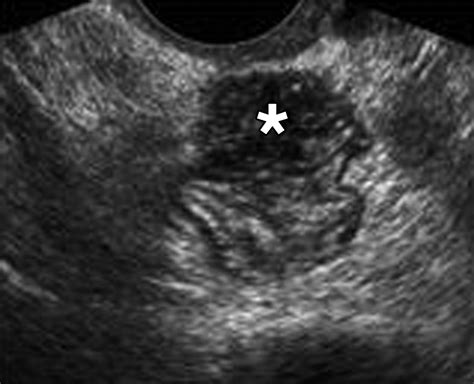

The Posterior Cul De Sac is a small, pouch-like structure found at the end of the rectum. It is part of the larger cul-de-sac system, which includes the anterior and lateral cul-de-sacs. The posterior cul-de-sac is particularly important because it is the lowest point in the pelvic cavity, making it a critical area for the accumulation of fluids and waste materials.

Anatomically, the Posterior Cul De Sac is situated between the rectum and the anal canal. It is lined with mucous membranes that secrete mucus, which helps to lubricate the rectum and facilitate the passage of stool. This mucus also plays a role in protecting the rectal lining from irritation and infection.

• MRI: An MRI uses magnetic fields and radio waves to create detailed images of the body's internal structures. This test can provide valuable information about the Posterior Cul De Sac and surrounding tissues.

• Advanced Imaging Techniques: New imaging technologies, such as high-resolution MRI and CT scans, are being developed to provide more detailed and accurate images of the Posterior Cul De Sac and surrounding tissues.